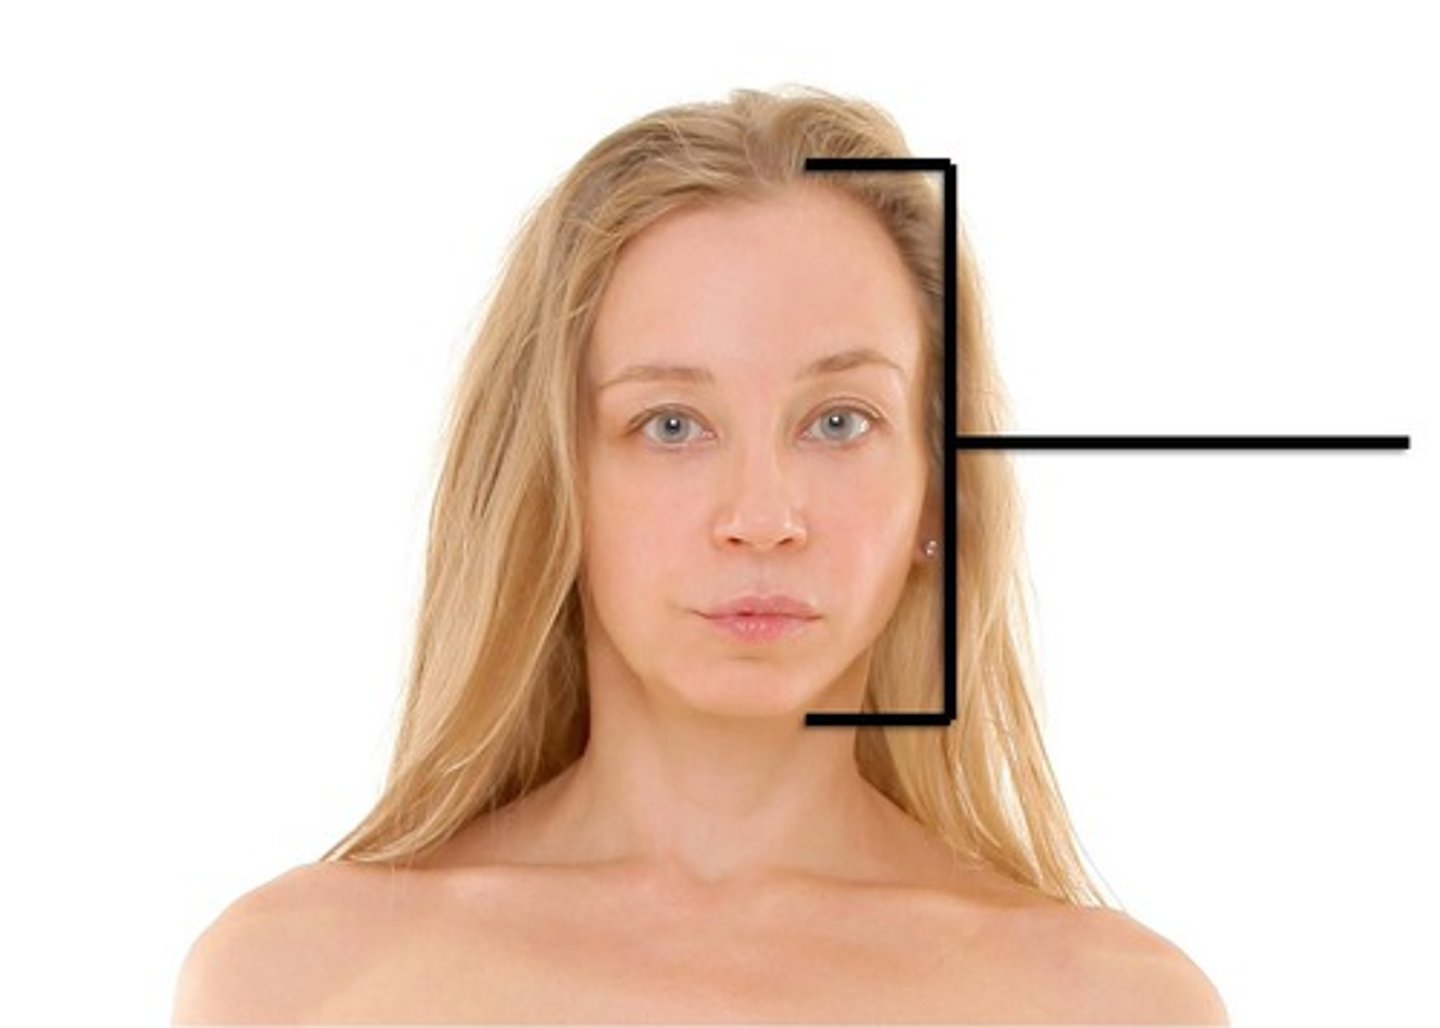

Buccal

Cheek area

Cephalic

head

Nasal

Nose area

Oral

Mouth

Orbital

Eye cavity